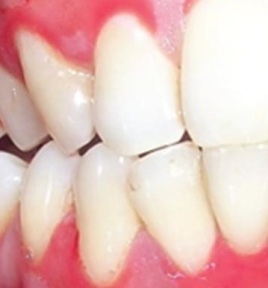

Cuando se acumulan bacterias en las encias, se genera una infección periodontal, que puede destruir el hueso que soporta los dientes, llevandolos a su pérdida total. Este nuevo gel Cariesend, combina el poder de sustancias naturales como la Papaína, y la resina de Dracaena que contiene, Tapsina, Flavonoides, Taninos y Catequinas. Con acción bactericida, antimicótica, antivírica, desinfectante y cicatrizante, que remueven las bacterias que causan la periodontitis, ayudando a disminuir el sangrado.

Después del cepillado y enjuague bucal de rutina, se puede aplicar el gel Cariesend, sobre la encia inflamada con un algodón y se deja actuar por 5 minutos antes de enjuagar. El gel Cariesend actúa con el poder de varias sustancias de origen natural como: papaína, tapsina, flavonoides, taninos y catequinas. Estos tienen acción comprobada en numerosos estudios como bactericida, antimicótica, antivírica, antiinflamatorio, desinfectante y cicatrizante. Tan pronto como pueda debe visitar al odontólogo, para determinar las causas y el tratamiento del problema periodontal. Con un estudio radiográfico el especialista determina si hay daño oseo y le indicará el tratamiento a seguir.